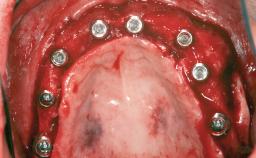

Shell Technique for Horizontal and Vertical Maxillary Bone Augmentation in a Partially Edentulous Patient with Aggressive Periodontal Disease

A 46-year-old woman was referred for treatment whose main complaints were mobility of her fixed partial dentures (right maxilla and left mandible) and periodontal bleeding during function. She also reported having taken systemic antibiotics to treat recurrent swelling in the area of the upper left molars. The patient had not seen a dentist for at least 2 years. She did not smoke and had no history of major systemic disease other than two minor orthopedic procedures some years back. The first-visit examination revealed poor plaque control, tooth mobility, periodontal disease, and a residual dentition widely associated with deep periodontal pockets.

# of Implants 3

Type of Implants One-Piece

Bone Augmentation Horizontal|Staged|Vertical